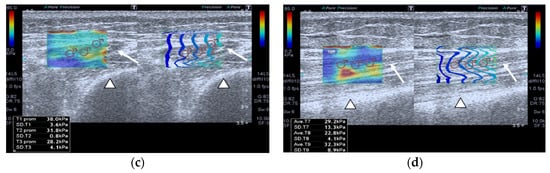

SWE images of a case and a healthy control are shown in Figure 1.

Figure 1.

Quadriceps rectus femoris (QRF) muscle ultrasound (US) scan and shear wave elastography (SWE) with several regions of interest (ROIs) (pink circles) measured across the muscle of a matched healthy control (63 years old). SWE shows high muscle elasticity. (a) Transversal QRF muscle (arrow) US scan, femur (arrowhead); (b) longitudinal QRF muscle (arrow) US scan, femur (arrowhead). Patient with multiorgan failure (67 years old). SWE shows muscle stiffness with several regions of interest (ROIs) (pink circles). (c) Transversal QRF muscle (arrow) US scan, femur (arrowhead); (d) longitudinal QRF muscle (arrow) US scan, femur (arrowhead).